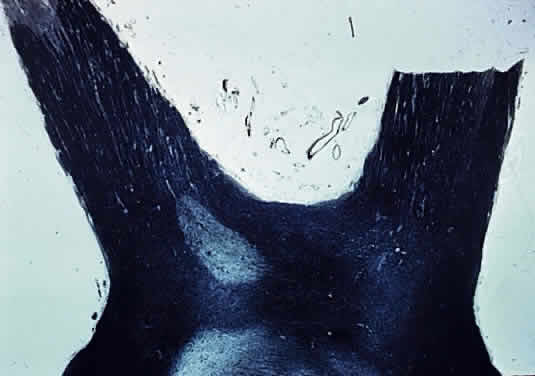

Fig. 1. Base of brain, showing optic nerves, chiasm, and tracts.